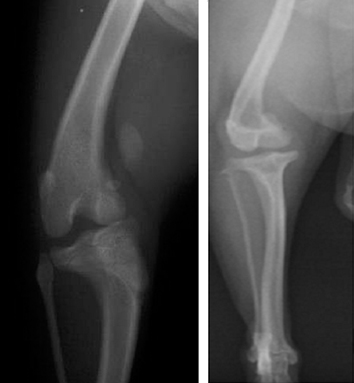

膝蓋骨脱臼の診断のためのX線検査においてはそのポジショニングも重要です。そのまま寝かせての位置ですと、どうしても膝の部分が浮いてしまいます。これらを避けるためには、上半身を起こして撮影します。またはVD(腰、後肢をうつ伏せの位置)でも有効です。

最後に上記の犬の膝蓋骨内側の脱臼(グレードⅣ)の手術計画の行程表の1例を示します。(Dr. Brian Beale.の指導による行程表)